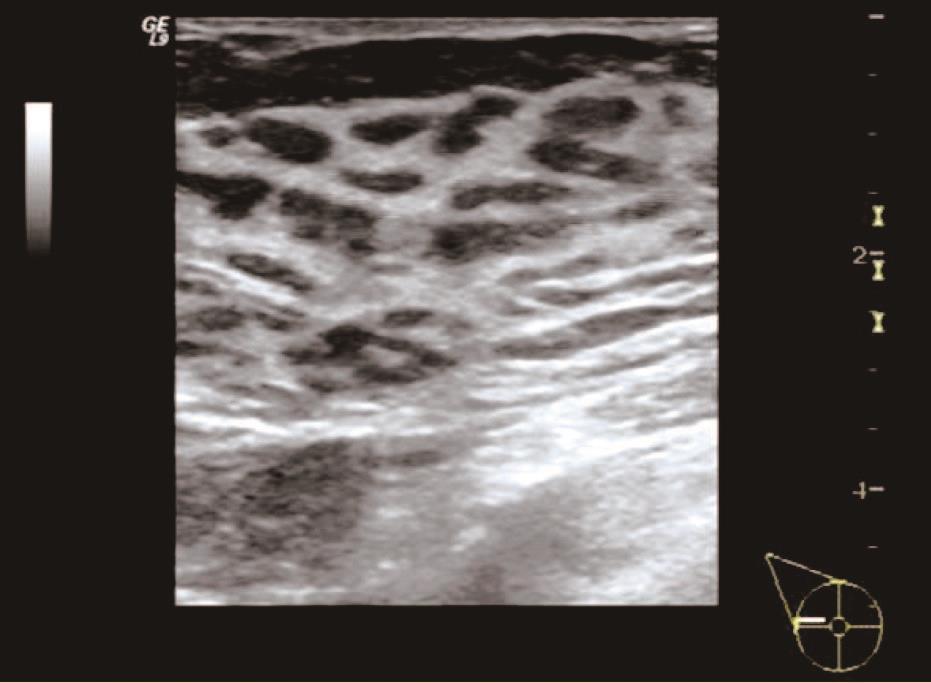

(1)单纯增生型:表现为乳腺腺体不同程度增厚,腺体内部结构稍紊乱,分布欠均匀,可见散在或弥漫分布的形态欠规则、边界欠清晰、大小不一的低回声区与稍高回声区相间,呈现“豹纹征”声像改变。可伴有钙化灶,钙化为较粗大沙砾状、杆状或小弧状,分布于乳腺局部,也可弥漫分布于整个乳腺,其内未见彩色血流信号或少许点状彩色血流信号,无明显囊肿及结节。